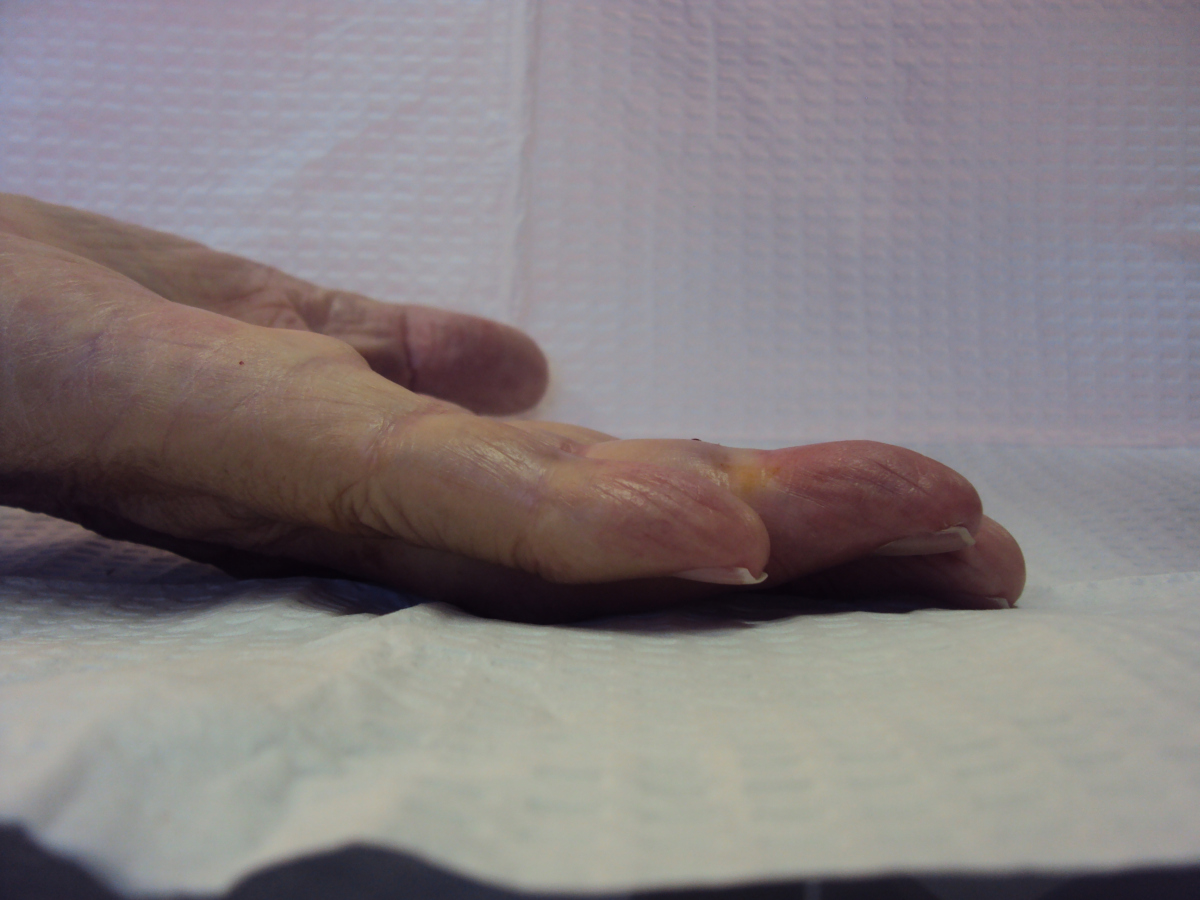

57 year old right handed man with a 22 year

history of Dupuytren disease affecting his

left small finger.

Highslide Highslide

Planning of portals (dots) and nodule steroid

injection sites (circles).

Radiograph of affected finger, 90° contracture.

End of Procedure. Minimal improvement, but the

joint felt rubbery to passive stretch, and so he

was treated with a night time static extension

splint. He had progressive improvement.

18 months later, improvement persists.